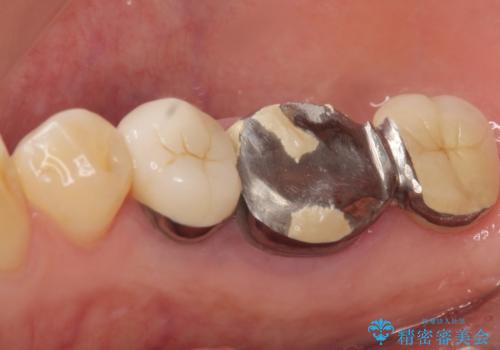

精査したところ、右下の奥歯(右下6)は割れており保存不可能な状態でした。

患者様のご希望により、右下大臼歯2本(右下76)のインプラント治療、右下小臼歯(右下5)の根管治療及び補綴治療を行いました。

割れていた歯の周囲組織の炎症が強く、骨の厚みが薄かったため、インプラント埋入時に骨増生(GBR)を行いました。